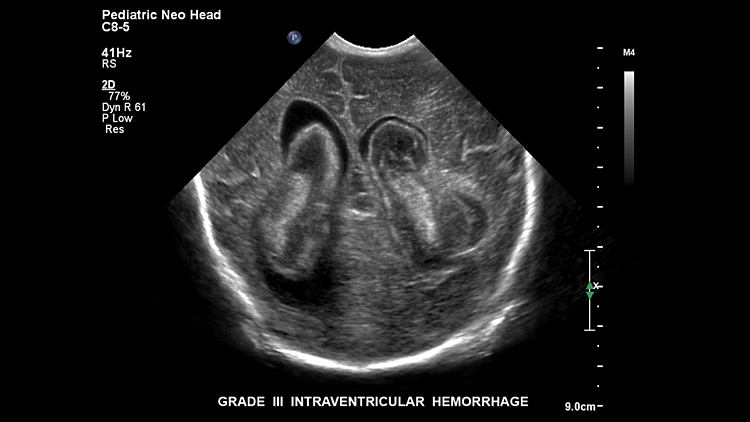

Внутрижелудочковое кровоизлияния, C8-5